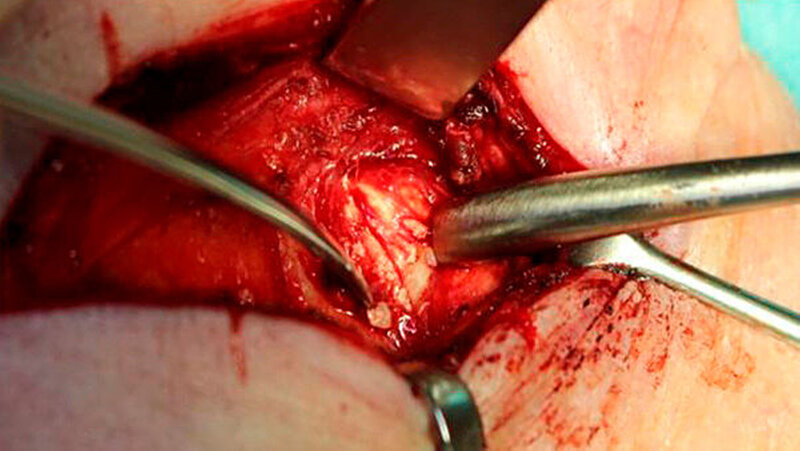

Das linke Kiefergelenk wurde über einen präaurikulären-temporalen Zugang unter Schonung des N. fazialis dargestellt. Nach Sichtbarwerden der deutlich verdickten Gelenkkapsel erfolgte die Inzision circa zwei Millimeter unterhalb der Gelenkgrube und Eingehen in den oberen Gelenkspalt (Abbildungen 5 und 6). Mithilfe der Schere wurde nun die Adhärenz des Discus artikularis von der Gelenkkapsel scharf getrennt und damit in den unteren Gelenkanteil eingegangen.

Jetzt wurde der zum Teil intraartikulär und zum Teil in der verdickten Gelenkkapsel liegende korpuskuläre Gelenkkörper unter ausgiebiger Spülung der Gelenkkapsel entfernt. Danach ließ sich der stark deformierte Gelenkkopf erkennen (Abbildung 7). Mithilfe von Diamantkugeln und einer maschinell betriebenen Feile wurde der Gelenkkopf ausgiebig modellierend osteotomiert und das Gelenk erneut inspiziert.

Die sich in situ befindlichen Fremdkörper wurden mit einem kleinen scharfen Löffel entfernt und das Gelenk nochmals gespült (Abbildung 8). Anschließend erfolgte eine adaptierende Naht der Gelenkkapsel und das Einbringen einer 8-er Redon-Drainage in die Wundhöhle. Nun erfolgten die Subkutan-Naht sowie die Hautnaht und das Anlegen eines sterilen Verbandes. Die entfernten Fremdkörper wurden zur patho-histologischen Untersuchung in Formalin aserviert und versandt.